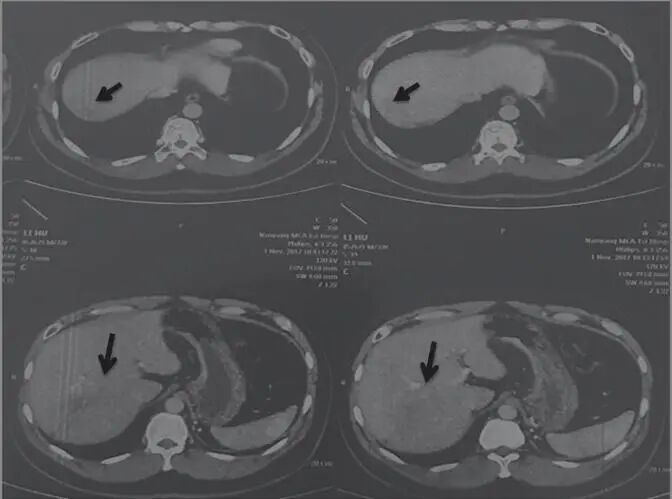

乙肝病史10年,2016年5月7日查AFP 989.8ng/mL,肝右叶巨大占位性病变(图1),考虑肝癌,大小约15cm×13.2cm,没有进行放疗、化疗和介入疗法。治法:舒少阳,散结聚,健脾胃,清湿热,宁心神

图1 舒达少阳防治肿瘤验案初诊CT结果